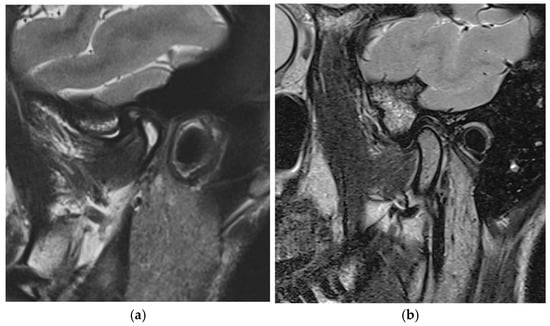

3.1. MRI Evaluation of Therapeutic Position (Figure 8)